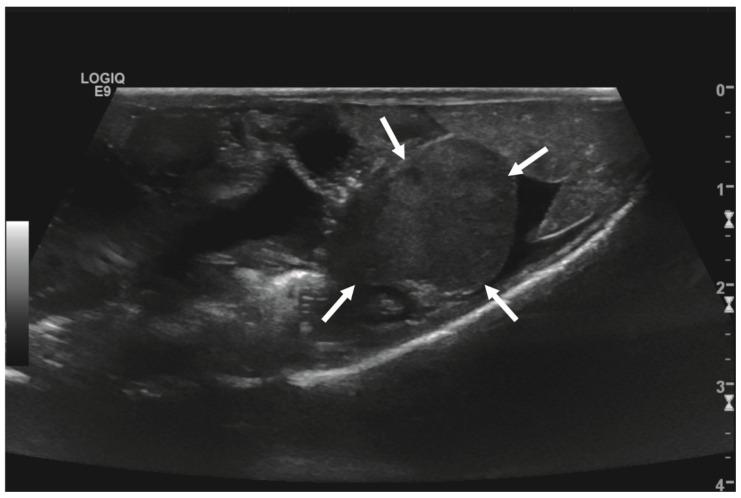

An adult, 362 g, male, intact inland bearded dragon () was admitted to a veterinary clinic due to a temporary cloacal prolapse and a two-week history of reduced overall condition and forage intake. Physical examination revealed an approximately 2 × 1 cm round-shaped, rigid intracoelomic tissue mass. Multiple sand deposits were present on the cloacal mucous membranes, though no signs of cloacal prolapse were present. The lizard was otherwise responsive but showed reduced body tension and movement behavior. Initial fecal examination revealed a high-grade oxyuriasis. A 2 × 1.5 cm sized intracoelomic, well-vascularized, round-shaped mass was subsequently visualized by ultrasonography. After a two-day stabilization therapy, the intracoelomic mass was removed by performing a standard ventral coeliotomy under general anesthesia. Histopathological examination of the excised mass revealed an acinar pancreatic adenocarcinoma with infiltration of the peritumorous connective soft tissue. The lizard remained at the clinic for a further seven days. Its postsurgical condition improved slowly. However, the lizard started regular forage intake 10 days after surgery, and general behavior enhanced constantly within the following three weeks. The animal was presented for a follow-up six weeks after surgery, showing bright and alert behavior with no signs of disease or illness. The lizard was re-examined 20 months after the initial presentation due to a reduced overall condition and reduced food intake. Blood chemistry evaluation revealed markedly decreased protein parameters, and moderate ascites was identified ultrasonographically. A distinct association with the preceding neoplastic disease could not be made, and the lizard returned to its regular condition under supportive therapy within three weeks. To the authors' knowledge, this is the first report of successful treatment of a pancreatic carcinoma in a bearded dragon.

一只体重362克的成年雄性内陆鬃狮蜥()因暂时性泄殖腔脱垂以及整体状况和采食量下降两周的病史被送至一家兽医诊所。体格检查发现腹腔内有一个约2×1厘米的圆形坚硬组织肿块。泄殖腔黏膜上有多处沙粒沉积,但未出现泄殖腔脱垂迹象。这只蜥蜴反应灵敏,但身体张力和活动行为有所减弱。初次粪便检查显示重度蛲虫感染。随后通过超声检查发现一个大小为2×1.5厘米、腹腔内、血管丰富的圆形肿块。经过两天的稳定治疗后,在全身麻醉下通过标准腹中线剖腹术切除了腹腔内肿块。对切除肿块进行组织病理学检查,结果显示为腺泡状胰腺腺癌,伴有肿瘤周围结缔组织软组织浸润。这只蜥蜴在诊所又待了七天。其术后状况恢复缓慢。不过,蜥蜴在术后10天开始正常采食,在接下来的三周内总体行为持续改善。术后六周对该动物进行随访,它表现出精神饱满、警觉,没有疾病迹象。因整体状况和食物摄入量下降,在初次就诊20个月后对这只蜥蜴再次进行检查。血液生化评估显示蛋白质参数明显降低,超声检查发现中度腹水。无法确定其与先前肿瘤疾病有明显关联,在支持性治疗下,这只蜥蜴在三周内恢复到正常状态。据作者所知,这是关于成功治疗鬃狮蜥胰腺癌的首例报告。